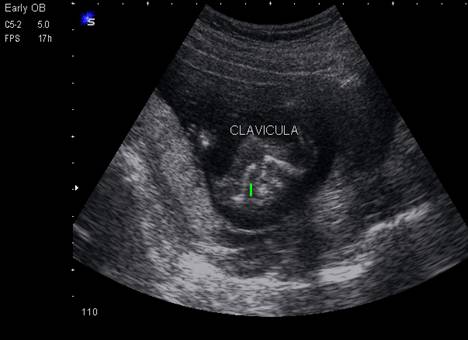

Claviculele se pun in evidenta intr-un plan transvers al gatului, cu evaluarea simetriei acestora.

Fig. nr. 170. Cele doua clavicule hiperecogene, avand curbura caracteristica in forma literei S